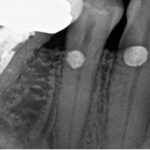

At our endodontic practice in St. Petersburg, Florida, we often treat patients with root resorption, a condition where parts of a tooth’s structure start to break down. In most cases, this happens to a single tooth. But sometimes, we see something more unusual: bilaterally symmetrical resorption. That means the same teeth on both sides of the mouth are affected, often in similar ways.

Over several years, we followed a patient with resorption in the same three teeth on both the left and right sides. Here’s how it progressed:

- The first molars on both sides had the largest areas of damage. The resorption was located on the cheek side (buccal) of the mesial root and extended into the furcation, the space where the roots meet. Because of the size of the lesions, root canal treatment (RCT) was necessary for both molars.

- The bicuspids (premolars) and cuspids (canines) also showed signs of resorption, but the damage was much smaller. These teeth did not need root canals.